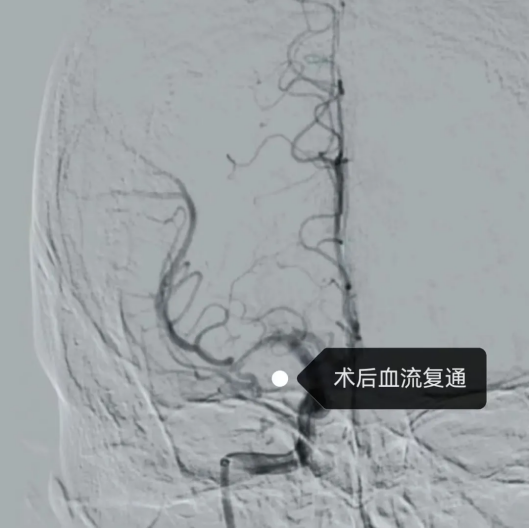

(术中、后影像)

最终,在团队娴熟配合与精准操作下,手术顺利完成。术后患者肢体肌力及语言功能均恢复良好,NIHSS评分显著改善,目前已基本恢复正常生活能力,治疗效果良好。